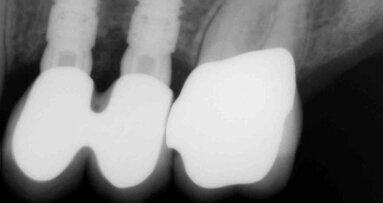

Fig. 6 - Fotografia frontale scattata prima della seduta di igiene orale professionale (Guided Biofilm Therapy).

Fig. 7 - Fotografia frontale scattata dopo la seduta di igiene professionale mediante l’utilizzo del sistema Airflow® Prophylaxis Master (EMS®) con polvere a base di eritritolo® e ablatore a ultrasuoni con punta perioslim (PS, EMS®).

Fig. 8 - Rilevamento del colore a tempo zero utilizzando la scala “Vita” D3.

Fig. 9 - Colore post sbiancamento professionale utilizzando la scala “Vita” A2.

Fig. 10 - Colore finale utilizzando la scala “Vita” A1.